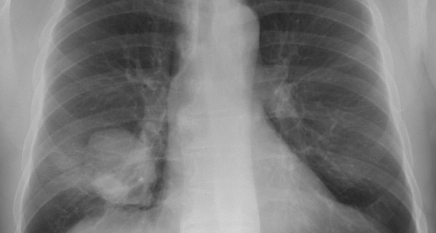

Unklarer Rundherd der Lunge und rezidivierendes Fieber. Diagnose, Komplikationen, Therapie und Verlauf.

Was dieser Kurs von Ihnen verlangt Ein intrapulmonaler Rundherd soll diagnostisch abgeklärt werden.

Rezidivierendes Fieber erschwert die Therapie. Der behandelnde Arzt entscheidet, welche diagnostischen und therapeutischen Schritte zur treffenden Diagnose und erfolgsversprechenden Therapie führen.